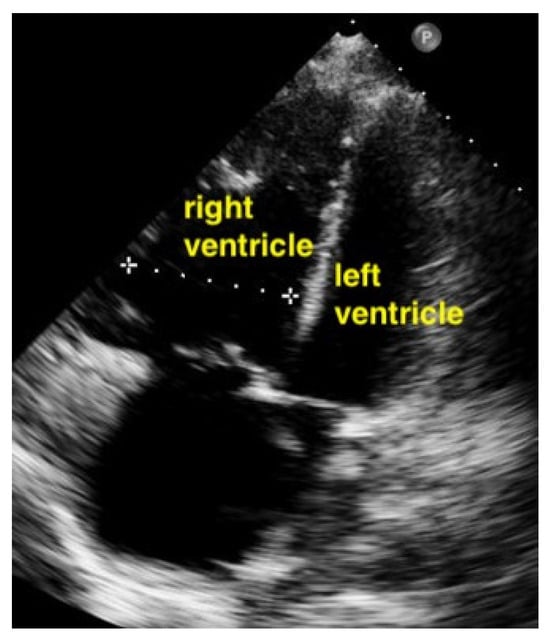

7.2.3. Pulmonary Embolism

A pulmonary embolism large enough to compromise circulation is typically seen in more centrally located pulmonary arteries, and the subsequent pressure overload results in an enlarged right ventricle. Normally, the right ventricle is slightly smaller than the left ventricle. The size of the right ventricle compared to the left ventricle is best estimated in the apical four-chamber view with a sector probe. However, the subcostal four-chamber view will also reveal an unusually easily seen right ventricle when dilation is present and should be an indication to investigate further. In the case of a central pulmonary embolism, the interventricular septum is typically flattened (apical four-chamber view) and shows a D-sign (parasternal short-axis view) [,] (Figure 15, Figure 16 and Figure 17).

Figure 15.

The right ventricle is much bigger than the left ventricle.

Figure 16.

Parasternal short-axis view. The pathologically increased right ventricular pressure pushes the septum to the left side during diastole, so that a D-shape of the left ventricle results (RV = right ventricle, LV = left ventricle).